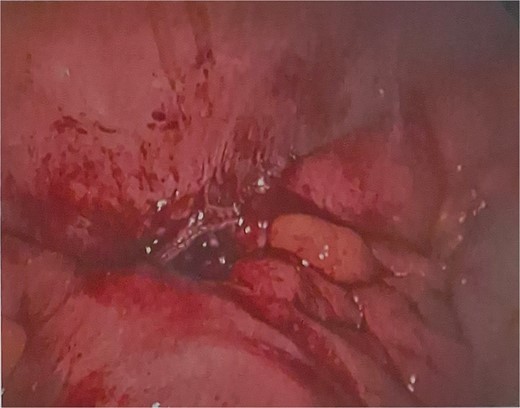

He was brought to theatre for a combined laparoscopic appendicectomy, drainage of peri-appendiceal abscess and cholecystectomy with intraoperative cholangiogram. Intraoperative findings included a 2 cm peri-appendiceal abscess cavity (Fig. 3) in keeping with pre-operative imaging. However, the gallbladder was gangrenous with a possible microperforation sealed by omentum (Fig. 4). Based on the intraoperative appearance, it was difficult to ascertain whether the abscess was due to primary appendicitis or whether the abscess was seeded from the cholecystitis and the appendix had become involved collaterally.

The cholecystectomy was performed first due to the evidence of gangrene. The gallbladder was decompressed, draining purulent bile, before dissection of the cystic duct and cystic artery to obtain the critical view of safety. Intraoperative cholangiogram was performed revealing a non-dilated biliary tree, clearly opacified upper ducts, no filling defects, and normal distal tapering with flow into duodenum. The gallbladder was dissected off the liver revealing a completely necrotic posterior wall.

The appendicectomy was then performed, locating the healthy base of the appendix and following its course to the thickened tip. The abscess cavity was opened and thoroughly washed out. The appendix was skeletonised, 2 endoloops were applied and the base was ligated with scissors between the loops. A 15 French Blakes drain was placed through the epigastric port, in the subhepatic space and down the right paracolic gutter. The patient was continued on piperacillin-tazobactam for 48 hours post-operatively.